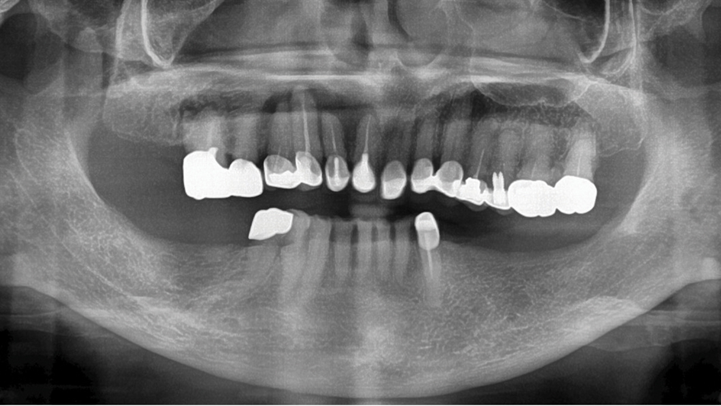

Clinical case: Delayed implant placement: sinus floor elevation by means of lateral

approach & implant placement with GBR

- Courtesy of Dr. Irfan Abas, Netherlands -

Clinical case: Installation of dental implants in complicated anatomic conditions using crest lifting methods

- Courtesy of Dr.Alexander Lysov, Russia -

AnyRidge, complicated anatomic conditions, crest lift, MICA Kit, Dr. Alexander Lysov, bone regeneration, GBR, #26, maxillary posterior